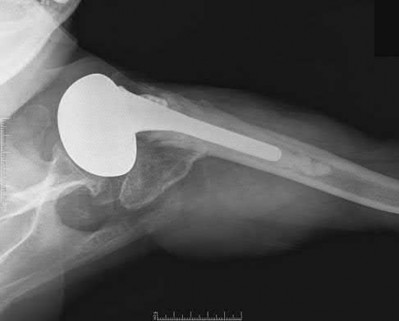

A 76-year-old male community ambulatory presented to clinic complaining of pain in the left groin that has been persistent for the last 8 months. Radiographs obtained from clinic are seen in Figure A. You suspect a femoral neck nonunion and obtain a CT scan which confirmed it. Which of the following statements is true?

A total hip arthroplasty (THA) after nonunion of a femoral neck fracture would provide the best long term outcomes in a 76-year-old male who is a community ambulator.

After nonunion of a femoral neck fracture, hemiarthroplasty and THA are good salvage option for the physiologically older patients. When deciding between these two options, THA is better for active and cognitively intact patients. THA is also indicated in patients with radiographic evidence of degenerative disease about the acetabulum. Hemiarthroplasty is advocated for patients who are older and less active.

Yang et al. retrospectively investigated the risk factors for nonunion in patients treated with cannulated screws. They reviewed 202 patients who had femoral neck fractures and were treated with internal fixation with cannulated screws. They identified that triangle configuration, displaced fracture, borderline or unacceptable reduction, and increased screw shaft subchondral purchase over the femoral neck were all risk factors for nonunion after internal fixation.

Inverted triangle configuration was found to increase rate of union.

Archibeck et al. retrospectively reviewed the outcomes of 102 THAs after failed internal fixation for a hip fracture (including both femoral neck and intertrochanteric). They concluded that the conversion of failed hip internal fixation has elevated risks compared to a primary THA, however, it may still be successful. The biggest concern for these patients postoperatively are periprosthetic fracture and dislocation.

Figures and Illustrations:

Figure A is an AP pelvic radiograph demonstrating a nonunion of a femoral neck fracture after suboptimal fixation with 3 cannulated screws in a triangle configuration.

Illustration A is an AP radiograph of the left hip in this patient following conversion to THA.

Illustration B is a radiograph demonstrating a valgus osteotomy. Illustration C shows an example of a femoral neck nonunion with varus malreduction.